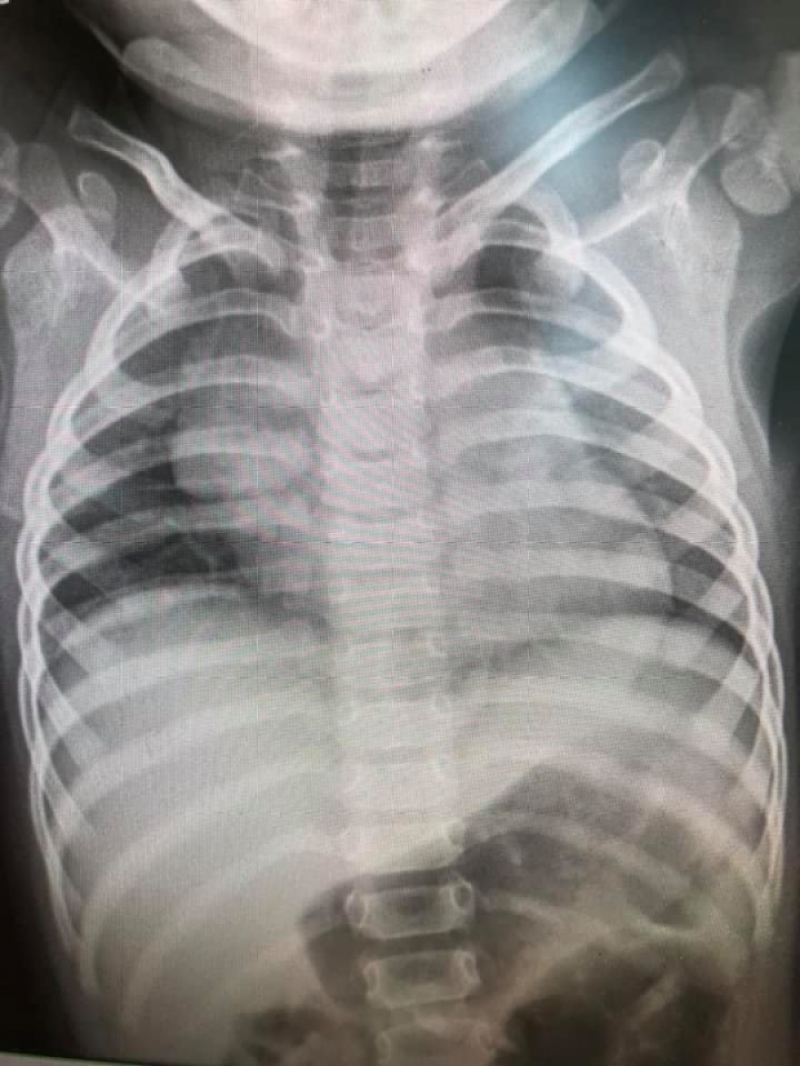

ด่วน เปิดภาพปอดจากผู้ป่วย ไวรัส RSV ปอดเเหว่งเป็นเเถบ

วันนี้ ( 6 พ.ย. 63 )เพจ Infectious ง่ายนิดเดียว ได้เปิดเผยภาพฟิล์มเอ็กซเรย์ปอด เด็กที่มี อาการจาก ไวรัส RSV พร้อมระบุข้อความว่า

" รวมฟิล์มปอดเด็กที่มีอาการจาก ไวรัส RSV 10 คน ที่แอดมิดวินิจฉัยหลอดลมอักเสบ ปอดอักเสบ

เปิดภาพปอดจากเด็กที่ป่วย ไวรัส RSV ชี้ทำหลอดลม-ปอดอักเสบ